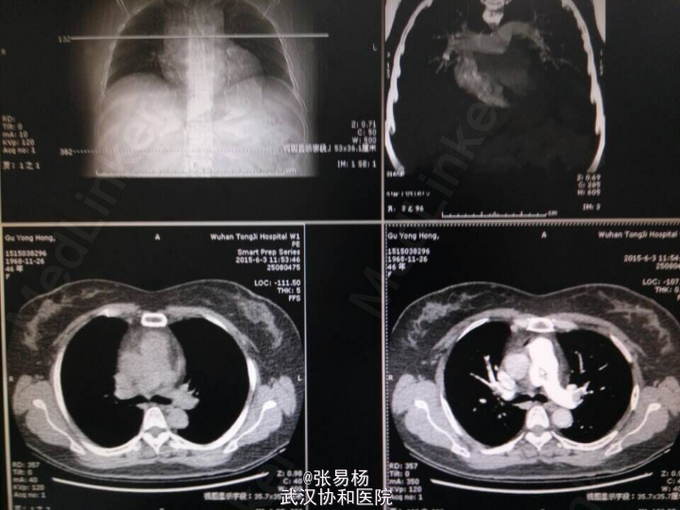

患者,女,47岁 主诉:双下肢胀痛不适10余天 现病史:患者于10余天前无明显诱因出现双下肢肿胀,有轻微压痛,久站及行走后加重,平卧后缓解,余无特殊症状。3天前门诊行双下肢彩超示:双侧小腿肌间静脉血栓形成。 既往有高血压病史3年余,口服利血平片,血压控制可余无特殊。

查体:双下肢水肿,指压征阳性,余无特殊。 辅检:肺动脉血管成像,CT-三维成像示:左肺动脉及其分支,右肺上叶肺动脉及其分支,右肺下叶后段肺动脉充盈缺损,考虑栓塞双肺血管纹理增强,考虑灌注不足所致。